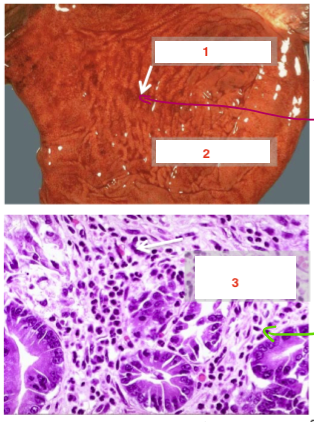

Below is a diseased stomach.

a. Name the condition

b.

a. Acute gastritis

Below is a normal stomach- name parts: